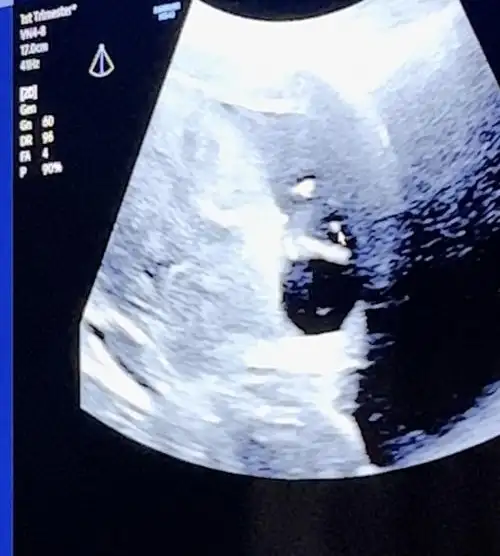

Oyyy sağlıkla gelsin inşallahKızlar ay o kadar heyecanlandım ki başım dönüyordu içeri girdiğimde sanki :)) elleri kolları oynuyordu hareket ediyordu o halini görünce ay o kadar duygulandım ki anlatamamdoktor yüzde 95 kız dedi böyle bir duygu yaşamadım hiç daha önce ya hala heyecanlayım Sağlıkla gelsin inşallah herkes güzel sağlıklı haberler alsın

Bu da fotolarımız birinde arkasını döndü birinde suratını kapattı çiçeğim

Var ama hiç belli olmuyorA var mı acaba ultrason fotoğrafı